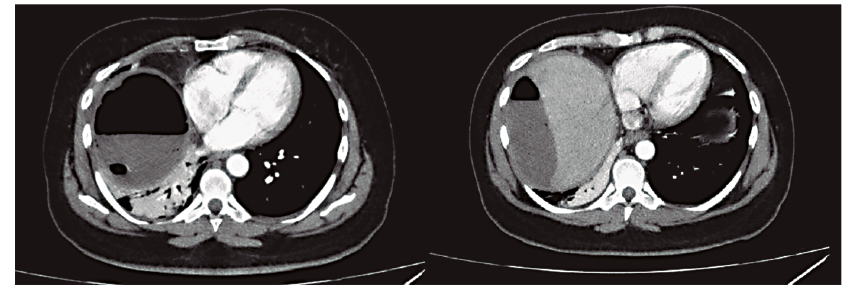

La paciente evolucionó con dolor abdominal leve en el epigastrio que mejoró con analgesia y amilasa post CPRE de 35 UI/l, por lo que se inició la alimentación y se le dio el alta 24 horas después del procedimiento. A las 96 horas reingresó por dolor abdominal severo a predominio del hemiabdomen superior, asociado a disnea clase funcional IV y dolor tipo puntada de costado. Negaba registros o equivalentes febriles y se encontraba hemodinámicamente estable. Laboratorio: hematocrito 39%, hemoglobina 12,7 g%, glóbulos blancos 18.100/mm3, amilasa 42 UI/l, lipasa 49,5 UI/l y hepatograma sin alteraciones. Se realizó una tomografía computada (TC) de abdomen y pelvis con contraste endovenoso, en la que se observó una colección hepática subfrénica derecha de 135 x 75 mm, con contenido particulado y burbujas aéreas, que elevaba la cúpula diafragmática e impresionaba de contenido hemático. Las vías biliares no estaban dilatadas (Figuras 2 y 3).